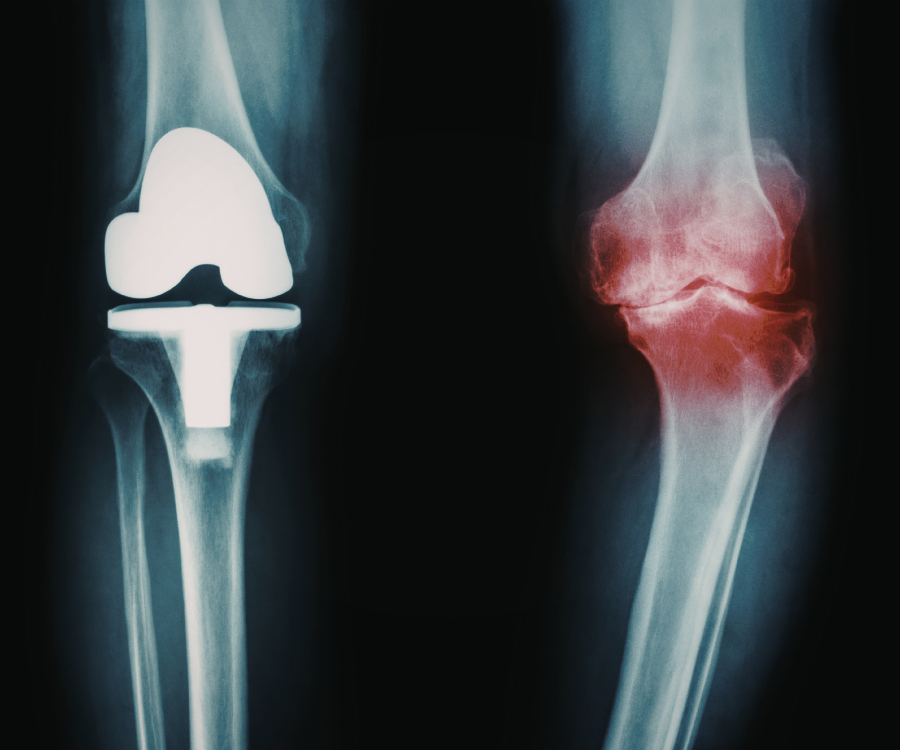

To understand why X-rays have limitations, it helps to know what they actually look for. X-rays are excellent at showing dense structures like bones. They can easily spot:

- Bone spurs (osteophytes).

- Narrowing of the space between joints (which indicates cartilage loss).

- Bone-on-bone contact in advanced stages.

However, arthritis doesn’t usually start in the bone. It often begins in the soft tissues—the cartilage, tendons, and the synovial lining—which are almost invisible on a standard X-ray.

- Cartilage is Invisible: Cartilage doesn’t show up on X-rays. Doctors have to “guess” how much cartilage is left by looking at how much space is between the bones.